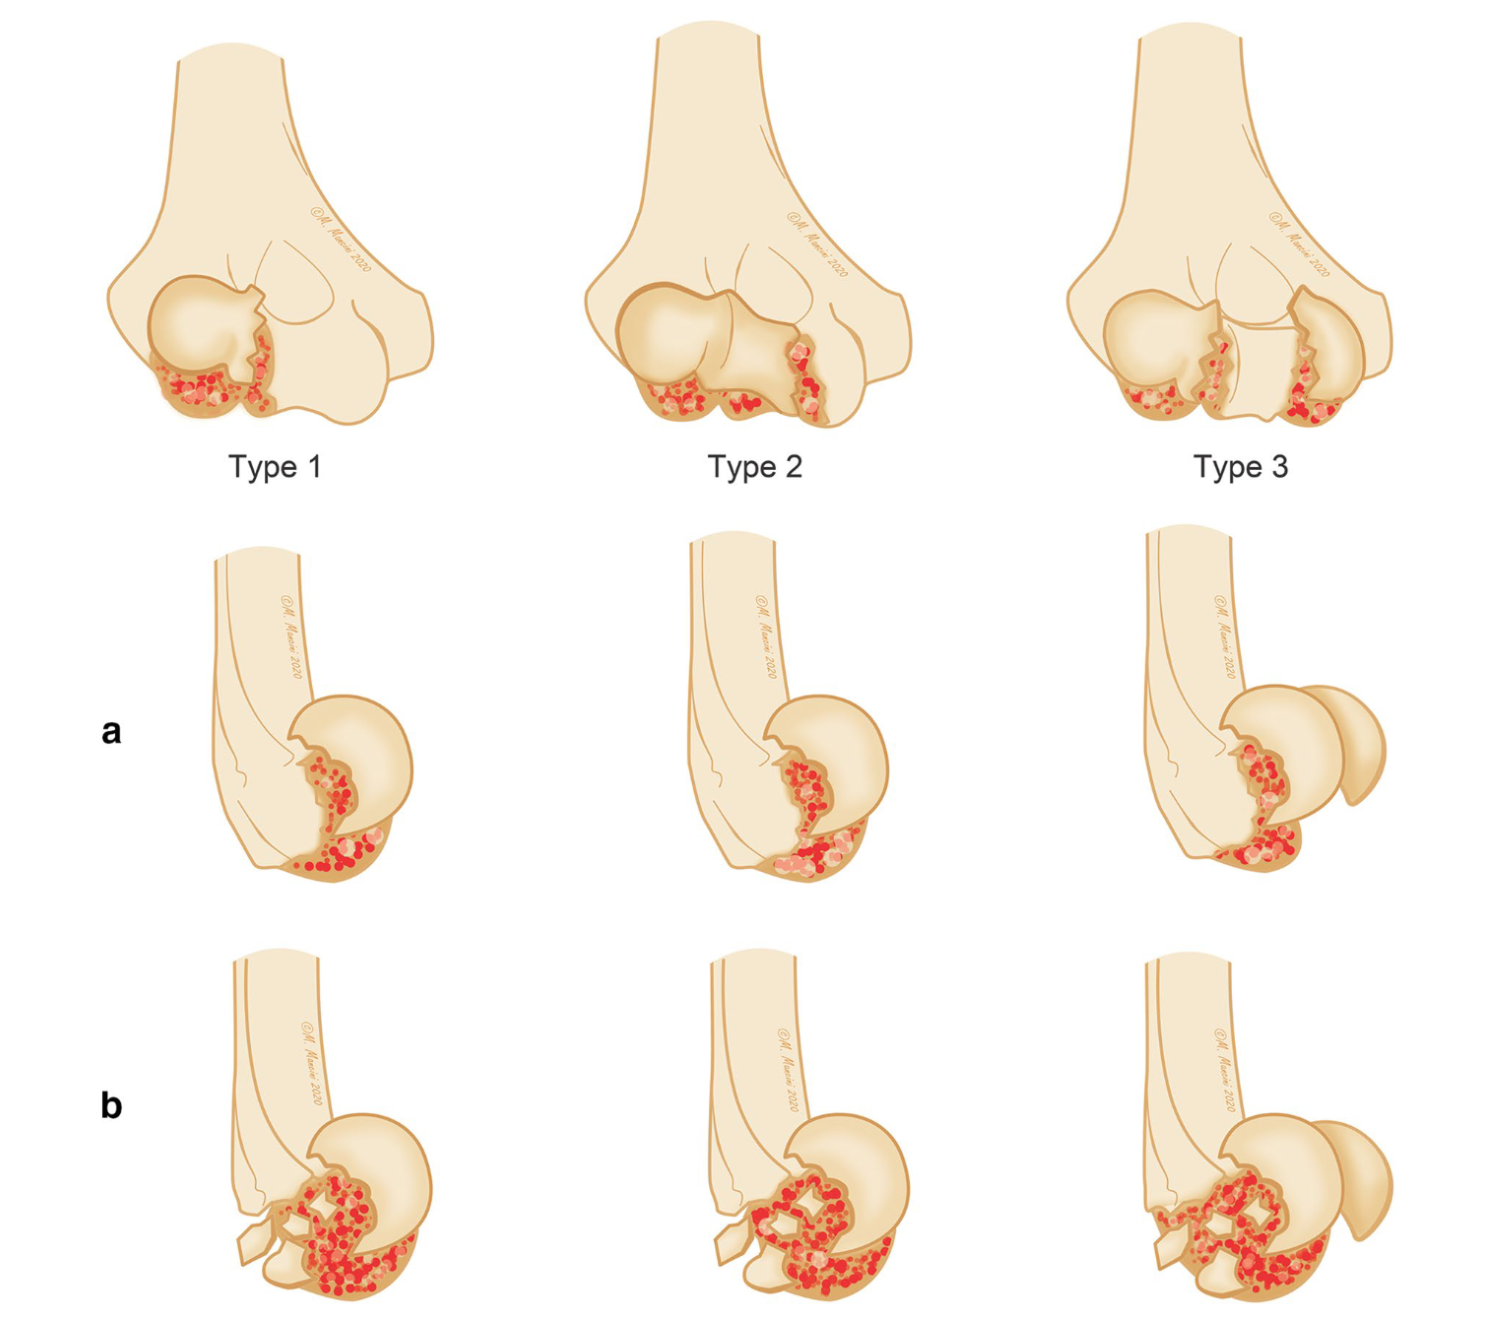

Coronal shear fractures of the distal humerus represent less than 1% of all elbow fractures [1], but this uncommon lesion could be burdened by high complications. This kind of injury is usually caused by low-energy fall on an outstretched hand or results from a spontaneous reduction of a posterolateral dislocation, where an axial force through the radial head involves the capitellum, with a variable extension to the trochlea or to the posterior aspect of the distal humerus [2, 3].

The complexity in surgical treatment is given by the small amount of subchondral bone available for a stable fixation [2], however conservative treatment with cast immobilization is no longer recommended because of the poor out- come and associated complications [8].

At present also the fragment excision is less used and can still be attempted for small unfixable fractures, despite a higher risk of residual instability, especially when the trochlea is involved [9, 10].

With the development of reconstructive techniques, better outcomes have been reported with surgical management based on open reduction and internal fixation [5, 12, 13].

The main purpose of surgery is to restore the congruity between articular surfaces through an anatomic reduction and stable fixation. Thanks to an early mobilization, this approach also reduces the incidence of elbow rigidity and secondary osteoarthritis. Though good-to-excellent results have been reported from several studies evaluating the functional outcomes of surgical treatment with internal fixation [11–13], no standard protocol has been proposed and limited data are available regarding outcomes and drawbacks. Purpose of this retrospective study is to evaluate the clinical and radiological outcome of coronal shear fractures treated with cannulated self-tapping headless screws, and to outline surgical tips and tricks for different fractures patterns.